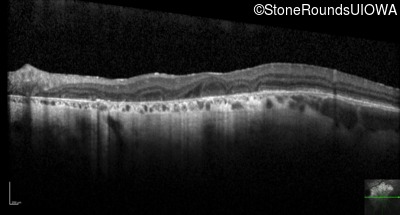

Optical Coherence Tomography - Left - 20/200

Exemplar / OCT Stack